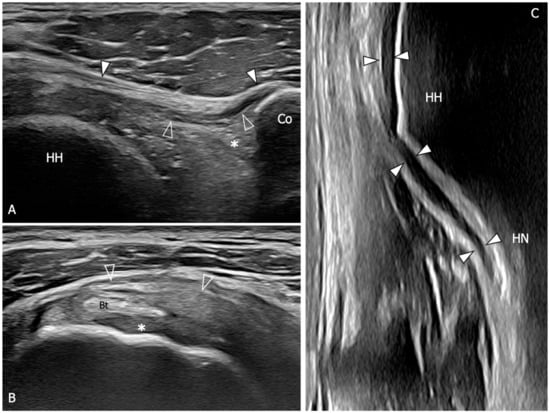

Figure 5.

Glenohumeral joint capsule and pericapsular ligaments, normal US findings. (A) Oblique transverse 18–5 MHz US image shows the normal thin and fibrillar appearance of the coracohumeral ligament (outlined arrowheads), which is demonstrated connecting the coracoid (Co) and humeral head (HH) in a deeper position respective to the coracoacromial ligament (arrowheads). Note the homogeneous and hyperechoic appearance of the subcoracoid fat (asterisk). (B) Short-axis 18–5 MHz US image shows the distal part of the coracohumeral ligament (outlined arrowheads) in the area of the rotator interval and the biceps pulley (asterisk). Bt, long head of the biceps tendon. (C) Longitudinal 18–5 MHz US obtained orienting the probe parallel to the humerus in the axillary region shows the inferior capsule (arrowheads) overlying the humeral head (HH) and folding over the humeral neck (HN).

Figure 6.

US findings in a 53 year old woman with adhesive capsulitis. (A) Oblique transverse 18–5 MHz US image demonstrates the markedly thickened coracohumeral ligament (outlined arrowheads), which has lost the normal fibrillar echotexture and appears homogeneously hypoechoic due to fibrotic changes and degeneration of the fibers. Note the presence of hypoechoic synovial tissue in the subcoracoid triangle (asterisk). Arrowheads, coracoacromial ligament. (B) Short-axis 18–5 Mhz US evidences the thickening and fibrotization of the coracohumeral ligament (arrowheads) and the biceps pulley (asterisks) in the rotator interval. (C) Longitudinal 18–5 MHz US image shows a significant thickening of the inferior capsule (arrowheads). HH, humeral head; Co, coracoid; Bt, long head of the biceps tendon; HN, humeral neck.